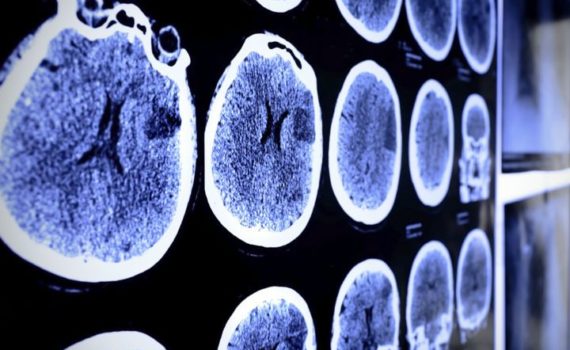

Badania pokazują, że użytkownicy cannabis mają mniejsze ryzyko doświadczenia udaru mózgu. Nowe badania przeprowadzone na University of Texas pokazują, że użytkownicy cannabis mają mniejsze ryzyko doświadczenia udaru mózgu. Nowe badanie pokazuje, że osoby stosujące cannabis są mniej podatne na udar […]